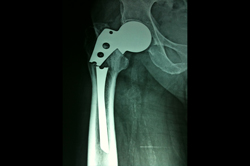

Intertrochanteric Fracture

Periprosthetic Fracture THR

Total Hip Replacement - THR